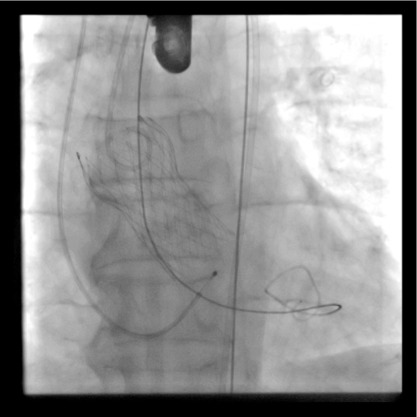

The final result after placing one stent in the lad artery, restoration of flow back to normal and halting the progress of the heart attack